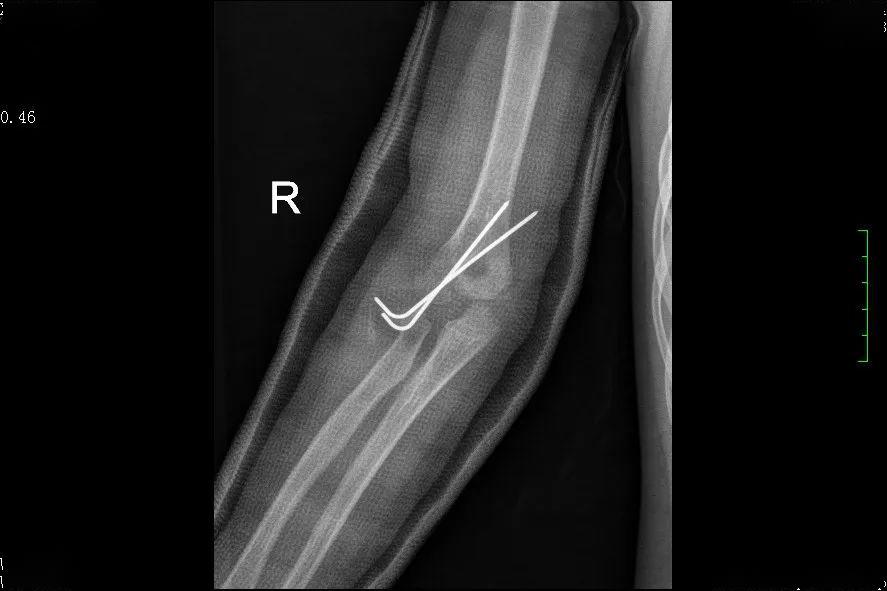

肱骨外髁骨折程度[s0]肱骨外髁骨折分型[s1]肱骨外髁骨折的临床表现[s2]肱骨外髁骨折Ⅲ型复位手法[s3]肱骨外髁骨折,保守治疗可以吗[s4]小儿肱骨外髁骨折[s5]儿童肱骨外髁骨折,医生不说你很可能永远都不会知道的[s6]不同类型的肱骨外髁骨折[s7]肱骨外髁骨折概述[s8]六、肱骨外髁骨折 - 图1[s9]六、肱骨外髁骨折 - 图2[s10]图片[s11]肱骨外髁骨折 m.haodf.com[s12]图片[s13]肱骨外髁骨折[s14]img[s15]肱骨外髁骨折.[s16]分期矫正儿童肱骨外髁骨折不愈合伴肘外翻畸形[s17]肱骨外髁骨折[s18]肱骨外髁骨折翻转90°,复位后克氏针或螺钉固定(自ao)[s19]右肱骨外髁骨折切开复位内固定术[s20]img[s21]img[s22]赵景新's media[s23]一例儿童右肱骨外髁骨折病例[s24]肱骨外髁骨折,保守治疗可以吗[s25]小儿肱骨外髁骨折[s26]肱骨外髁骨折固定[s27]肱骨外髁骨折 www.iiyi.com[s28]小儿肱骨外髁骨折的诊断和治疗[s29]右肱骨内外髁骨折[s30]图36-48 肱骨外髁骨折的不同程度移位 a型无移位;b型中度移位;c型完全移位伴旋转[s31]肱骨外髁骨折 www.haodf.com[s32]肱骨外髁骨折 www.haodf.com[s33]问:左肱骨外髁骨折,左肘关节脱位,6.[s34]儿童肱骨外髁骨折 - 小红书[s35]儿童肘关节损伤之--肱骨外髁骨折[s36]▲右侧肱骨外髁骨折闭合复位克氏针固定及石膏固定术后。“幸亏在掉落的[s37]肱骨外髁骨折 www.guahao.com[s38]肱骨头及外髁骨折,求诊治方案,手术还是非手术[s39]